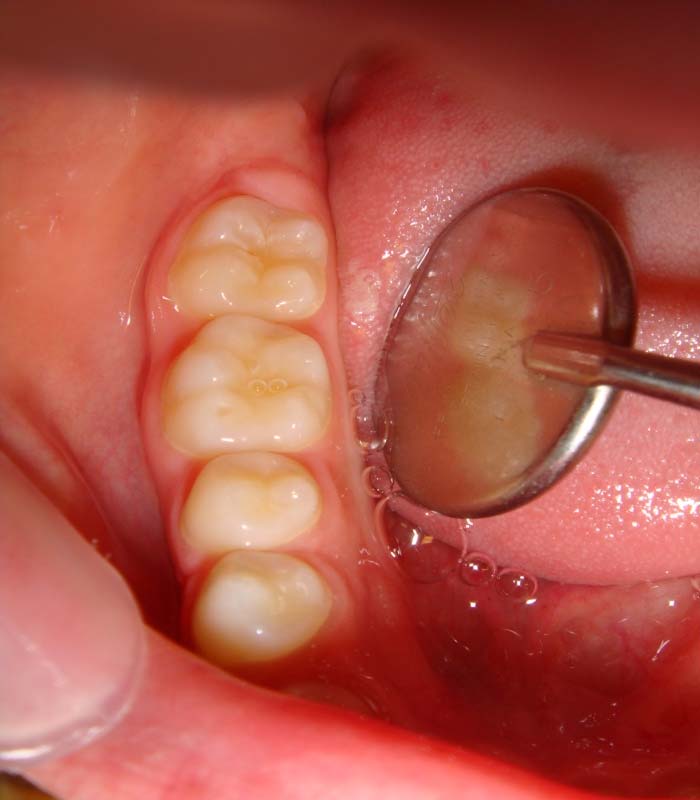

When a child is being examined assess the molars. As each cusp erodes a circle will appear on the cusp tip. If one circle is present less erosion has taken place than if the maximum number of five circles has taken place. Hence the name.

1 Circle (MB cusp of LR6)